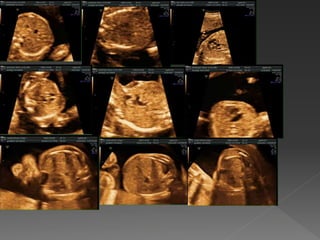

 DO Kalbinen önemli bölümüdür ve doğru değerlendirilmelidir • Büyük kardiyak malformasyonların %60’da anormal olarak görülür • Kalp; boyut, pozisyon, yapı ve fonksiyon açısından sistematik olarak analiz edilmelidir

 Normal kalptoraksın üçte biri kadar bir alan kaplar  Bu genellikle hareketli görüntü sırasında değerlendirilebilir Kardiyomegali Normal kalp boyutu

 Kalp toraksınsol tarafında yer alır  Normalde omurga ve sternum oryantasyon için kullanılabilir  Sol atrium normal kalpte en arka odacıktır, hemen önünde inen aorta yer alır, omurganın önünde görülür  Sağ ventrikül sternuma yakın görülür  Normal kalp apeksi sol ön göğüs duvarını işaret edecek şekilde  interventriküler septum, toraks orta çizgisine yaklaşık 45° (25- 70°) dik olarak yerleşir Normal kalp pozisyonu

 Her ikiatriyum ve ventrikül yaklaşık olarak eşit büyüklüktedir  Solda mitral ve sağda triküspit olmak üzere iki eşit AV kapak vardır  Sağ ventrikül apeksi sola göre daha trabekülerdir ve kalınlaşmış kas demeti (moderatör bant) içerir  Myokard etrafında normal olarak küçük miktarda perikardiyal sıvı bulunur ve koyu bir çizgi olarak görülür Normal 4 odacık ve kapaklar

 Crux (kalbinmerkezi) atriyoventriküler septum kavşağı ve mitral-triküspit kapakların septal yaprakcıklarının birleşimi ile oluşur  TK kapak, MK göre daha apikalde yer alır, bu nedenle crux içinde iki kapak farklı yerleşmiştir(off-setting)  Normal kalpte, farklı insersiyon sonucu, iki kapak crux boyunca düz çizgi oluşturmazlar Normal crux

 Normal kalpteventriküler septum apeksden crux’a kadar intaktdır  Primum atriyal septum crux’a bağlanır  Atriyal septumun orta üçde birlik alanında bir defekt vardır (foramen ovale)  Foramen ovale flebi sol atriumda görülür Foramen ovale

 Kalbin arkasındabir damar görülür (inen aorta), hemen orta hattın sol tarafında, omurga ile sol atriyumun arasındadır  Pulmoner venler, sol atriyumun arkasına bağlanır Pulmoner venler

 İki ventriküleşit  İki AV kapak serbest ve açıktır  Renkli doppler görüntüleme ile, her iki ventrikül eşit dolar ve önemli bir AV kapak yemezliği yoktur  A ve V senkronize şekilde ve düzenli çalışır Anormal sol ventrikül kontraktilitesi Normal ventrikül kontraktilitesi